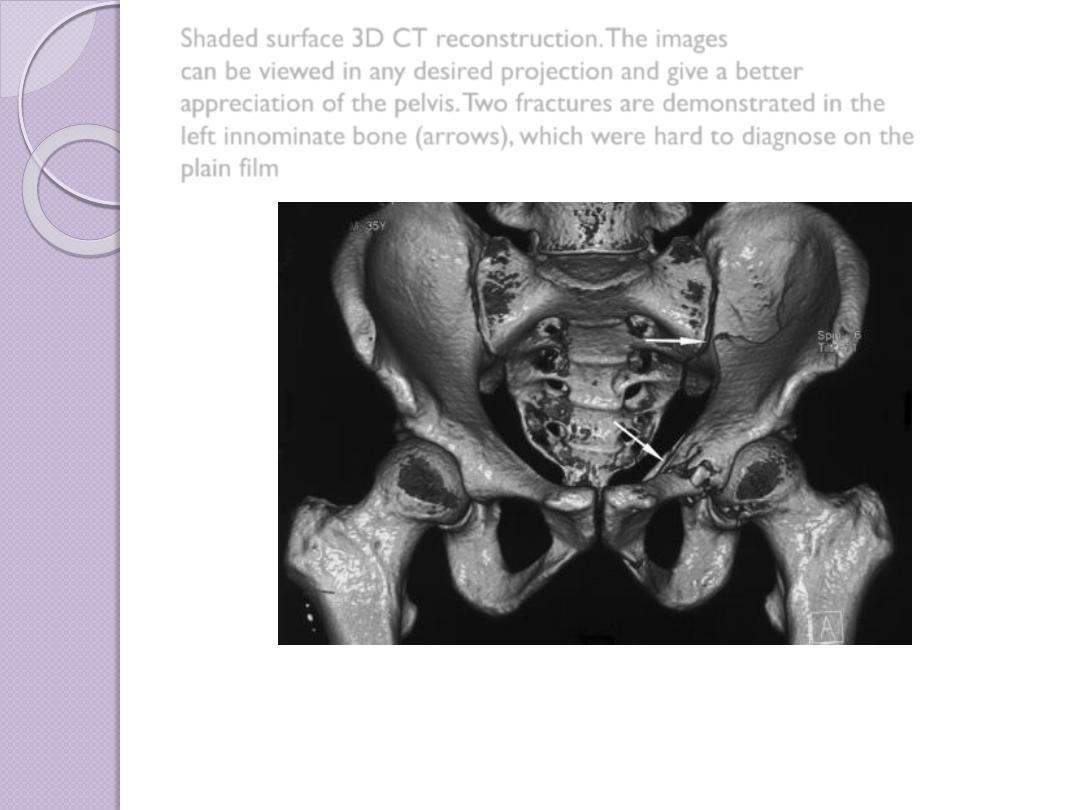

Shaded surface 3D CT reconstruction. The images

can be viewed in any desired projection and give a better

appreciation of the pelvis. Two fractures are demonstrated in the

left innominate bone (arrows), which were hard to diagnose on the

plain film